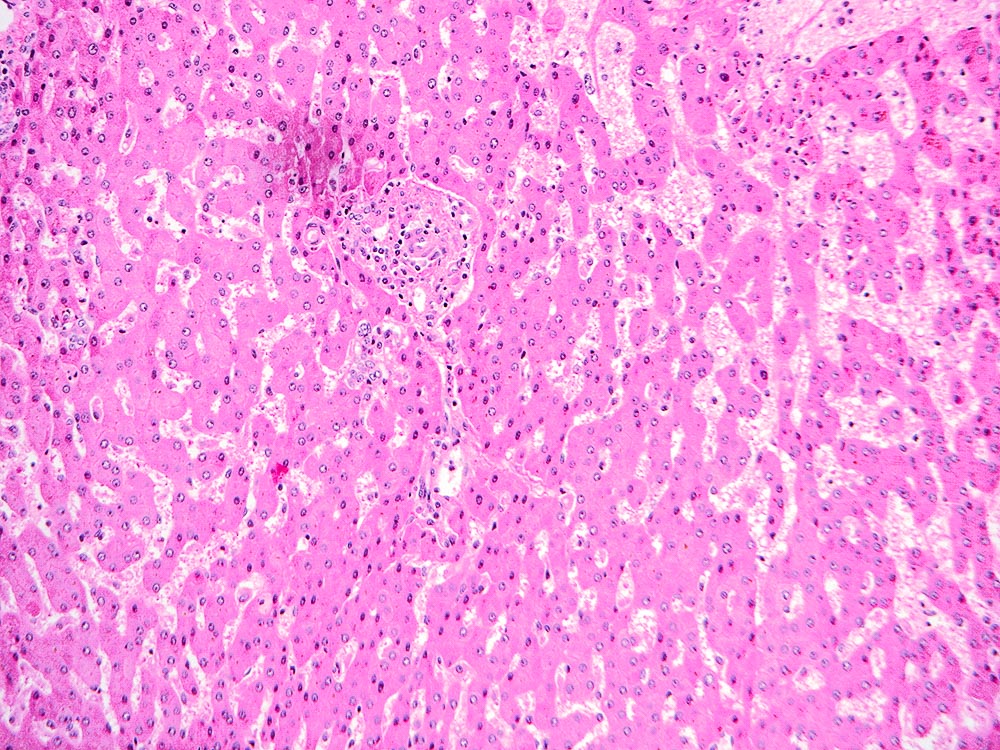

The explant showed a nodular liver with areas of sinusoidal dilatation, and occasional incomplete septae, but no evidence of cirrhosis. Rare florid ducts of PBC are present but there is mild ductopenia that came down to approximately just 20% of the terminal bile ducts; the larger bile ducts appear normal as are most of the small/terminal bile ducts. Several small portal tracts however have increased portal and occasionally periportal fibrosis and no visible portal veins. The larger portal tracts often have small portal veins when compared with the corresponding hepatic artery or bile duct, with thickening of the veins walls (obliterative portal venopathy). Reticulin stain demonstrates nodularity not bordered by fibrous septae, the edge of the nodules having compressed reticulin fibers (NRH). Sections from the hilum demonstrate major but non-occlusive portal vein thrombus.

Non-cirrhotic portal hypertension from a combination of nodular regenerative hyperplasia (NRH), portal vein thrombosis, and obliterative portal venopathy (OPV) in a patient transplanted for Primary Biliary Cirrhosis